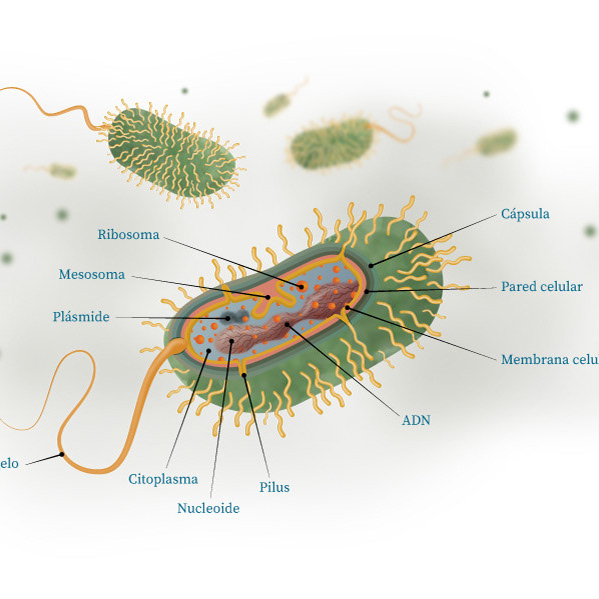

Infografía / Infectología

Infografía / Infectología